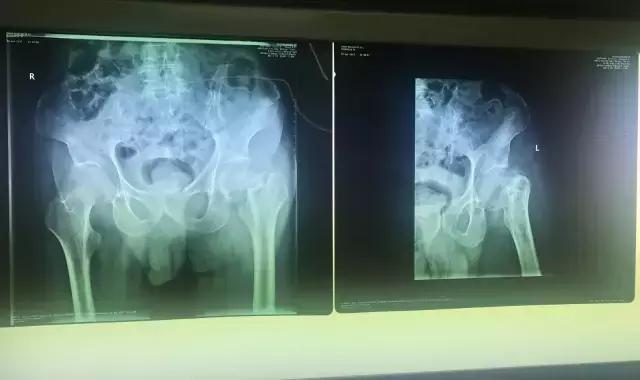

检查结果让老人和家属大吃一惊,原来老人的大胯已经骨折(股骨颈骨折),之前之所以还能勉强站立,是因为老年人对疼痛不是很敏感,再加上陈老先生的忍耐力比较强,所以才没有引起大家的重视。

谈到接下来的治疗方式,家属和医生都犯了难,老人骨折的地方特别特殊,这种股骨颈骨折很难自行愈合,还容易引起股骨头坏死。如果患者年轻一点,同样的病情,医生首先推荐的治疗方式是关节置换手术,因为置换后,患者4-6小时后就能够下床活动,但是鉴于老人毕竟已经92岁高龄,高龄对于手术本身就是一个危险因素,再加上老年患者身体多少有一些脉硬化、冠心病之类的基础病,万一在手术台上发生意外,怎么办?